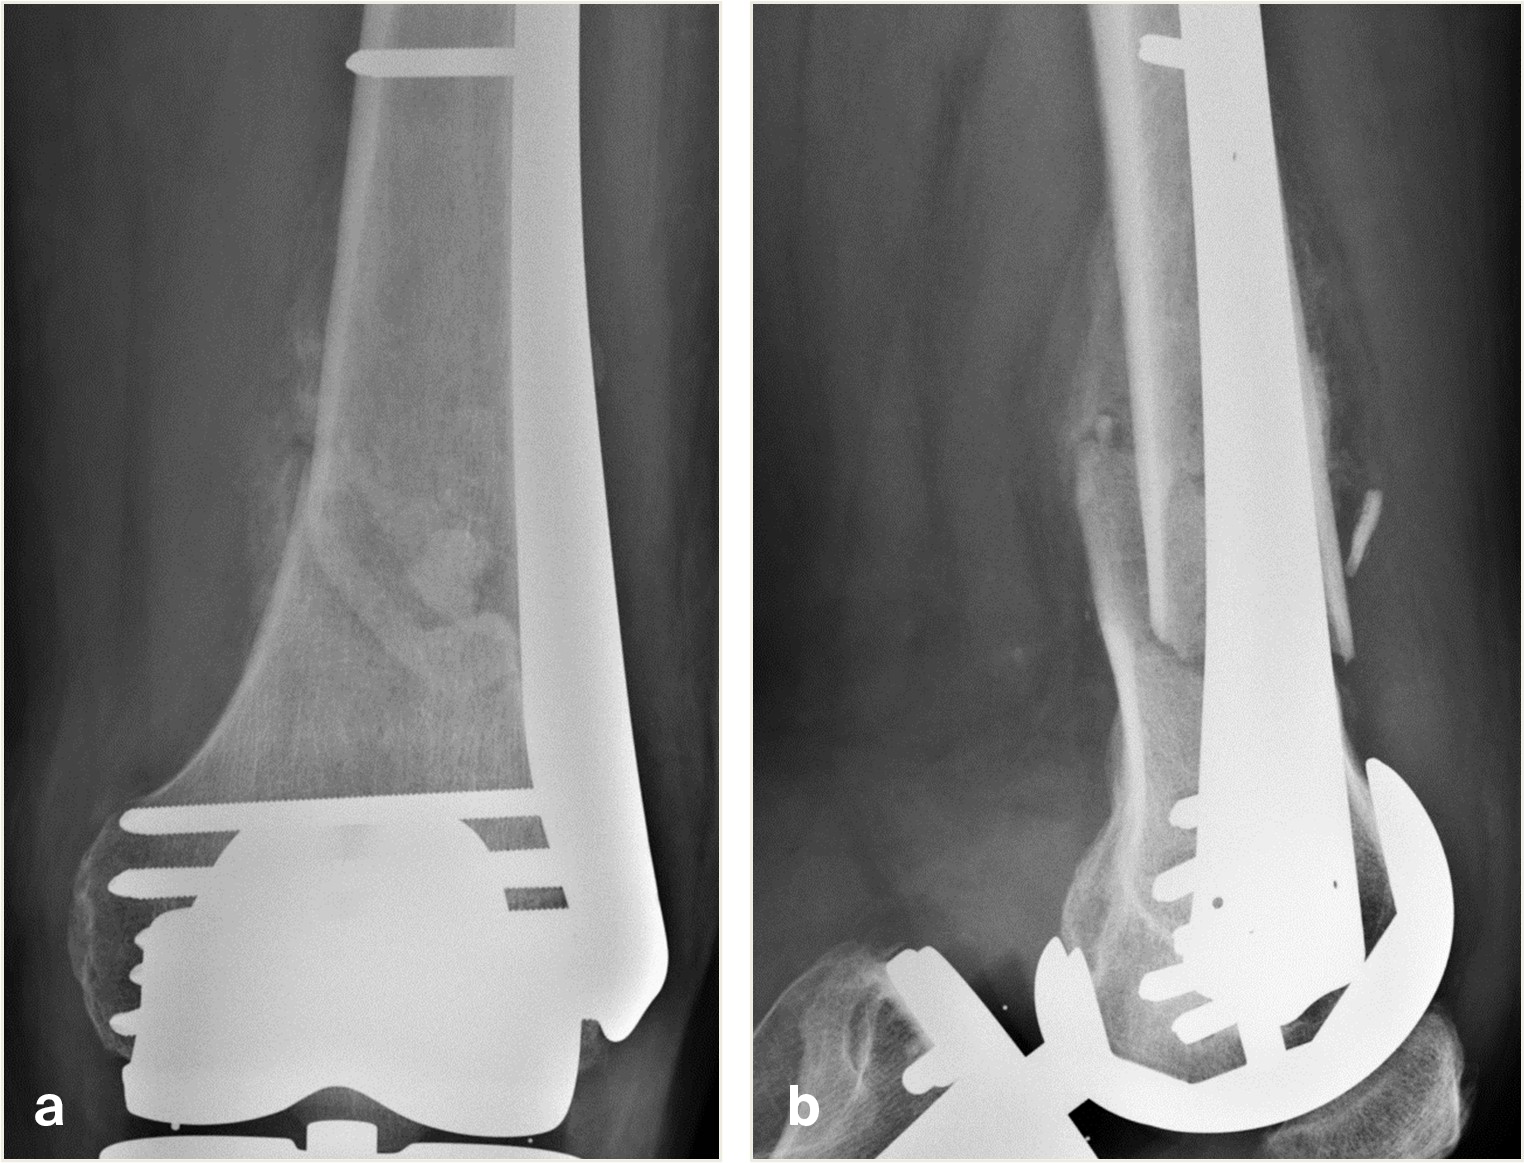

An 82-year-old man fell while climbing and sustained a periprosthetic distal femoral fracture (Fig 8). The fracture was reduced and then fixed with a Biphasic Plate DF (Fig 9). The patient was allowed immediate full weight bearing and presented with a decent amount of callus at the fracture site after 6 weeks (Fig 10).

The patient showed uneventful healing and returned to preoperative function 2.5 months postoperation. Figure 11 shows the callus formation 3 months postoperation.